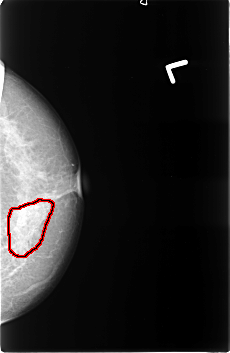

B_3397_1.LEFT_MLO

LEFT_MLO LINES 4536 PIXELS_PER_LINE 2976 BITS_PER_PIXEL 12 RESOLUTION 50 OVERLAY

FILE: B_3397_1.LEFT_MLO.OVERLAY

TOTAL_ABNORMALITIES 1

ABNORMALITY 1

LESION_TYPE CALCIFICATION TYPE PLEOMORPHIC DISTRIBUTION SEGMENTAL

LESION_TYPE MASS SHAPE FOCAL_ASYMMETRIC_DENSITY MARGINS ILL_DEFINED

ASSESSMENT 5

SUBTLETY 5

PATHOLOGY MALIGNANT

TOTAL_OUTLINES 1

BOUNDARY